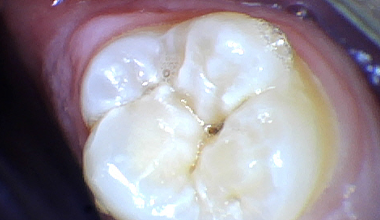

소구치대구치레진

충치치료 CASE

CASE 01

치료 전 -

치료 중 -

치료 후 -

2년 후